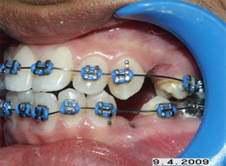

Correction of jaw positions during growth

In growing patients if the lower jaw is small in size or backwardly placed then the position of the lower jaw can be improved using certain removable appliances called Functional appliances. Not all patients are suited for this kind of treatment, case selection is important.

Again in growing patients sometimes the growth of jaws if improper can be restricted or encouraged using certain orthopedic appliances, which are metal frameworks from which elastics are engaged.

Appliances to correct jaw realtions